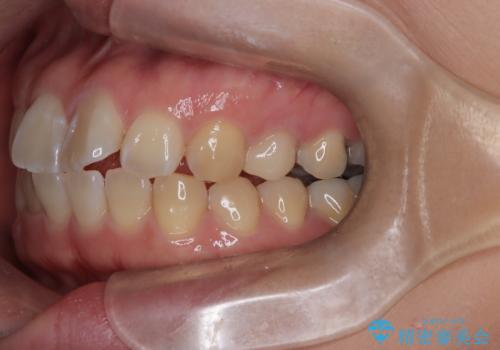

- 口元が出ている(突出している)ことを気にされて来院されました。精密な検査の結果、前歯を大きく後退させるスペースが必要と診断。患者様の**「前歯を下げたい」という強いご要望に応えるため、上下左右の第一小臼歯を抜歯し、そのスペースを利用して前歯を奥へ移動させる治療計画を立案しました。また、人目を気にせず治療できるよう、上顎に裏側矯正、下顎に表側矯正を組み合わせたハーフリンガル矯正**を提案しました。

今回の矯正治療では、前歯を大きく後退させるスペースを確保するため、計画通り上下左右の第一小臼歯を抜歯しました。装置には、上顎には目立たない裏側矯正(舌側矯正)を、下顎には透明な審美ブラケットを使用するハーフリンガル矯正を採用しました。抜歯によってできたスペースを最大限に活用し、前歯を効率よく後方へ移動。治療の結果、口元の突出感が大幅に解消され、Eライン(横顔の美しさの基準)も改善しました。人目を気にすることなく治療を完遂し、自信の持てる美しい横顔を獲得していただけました。